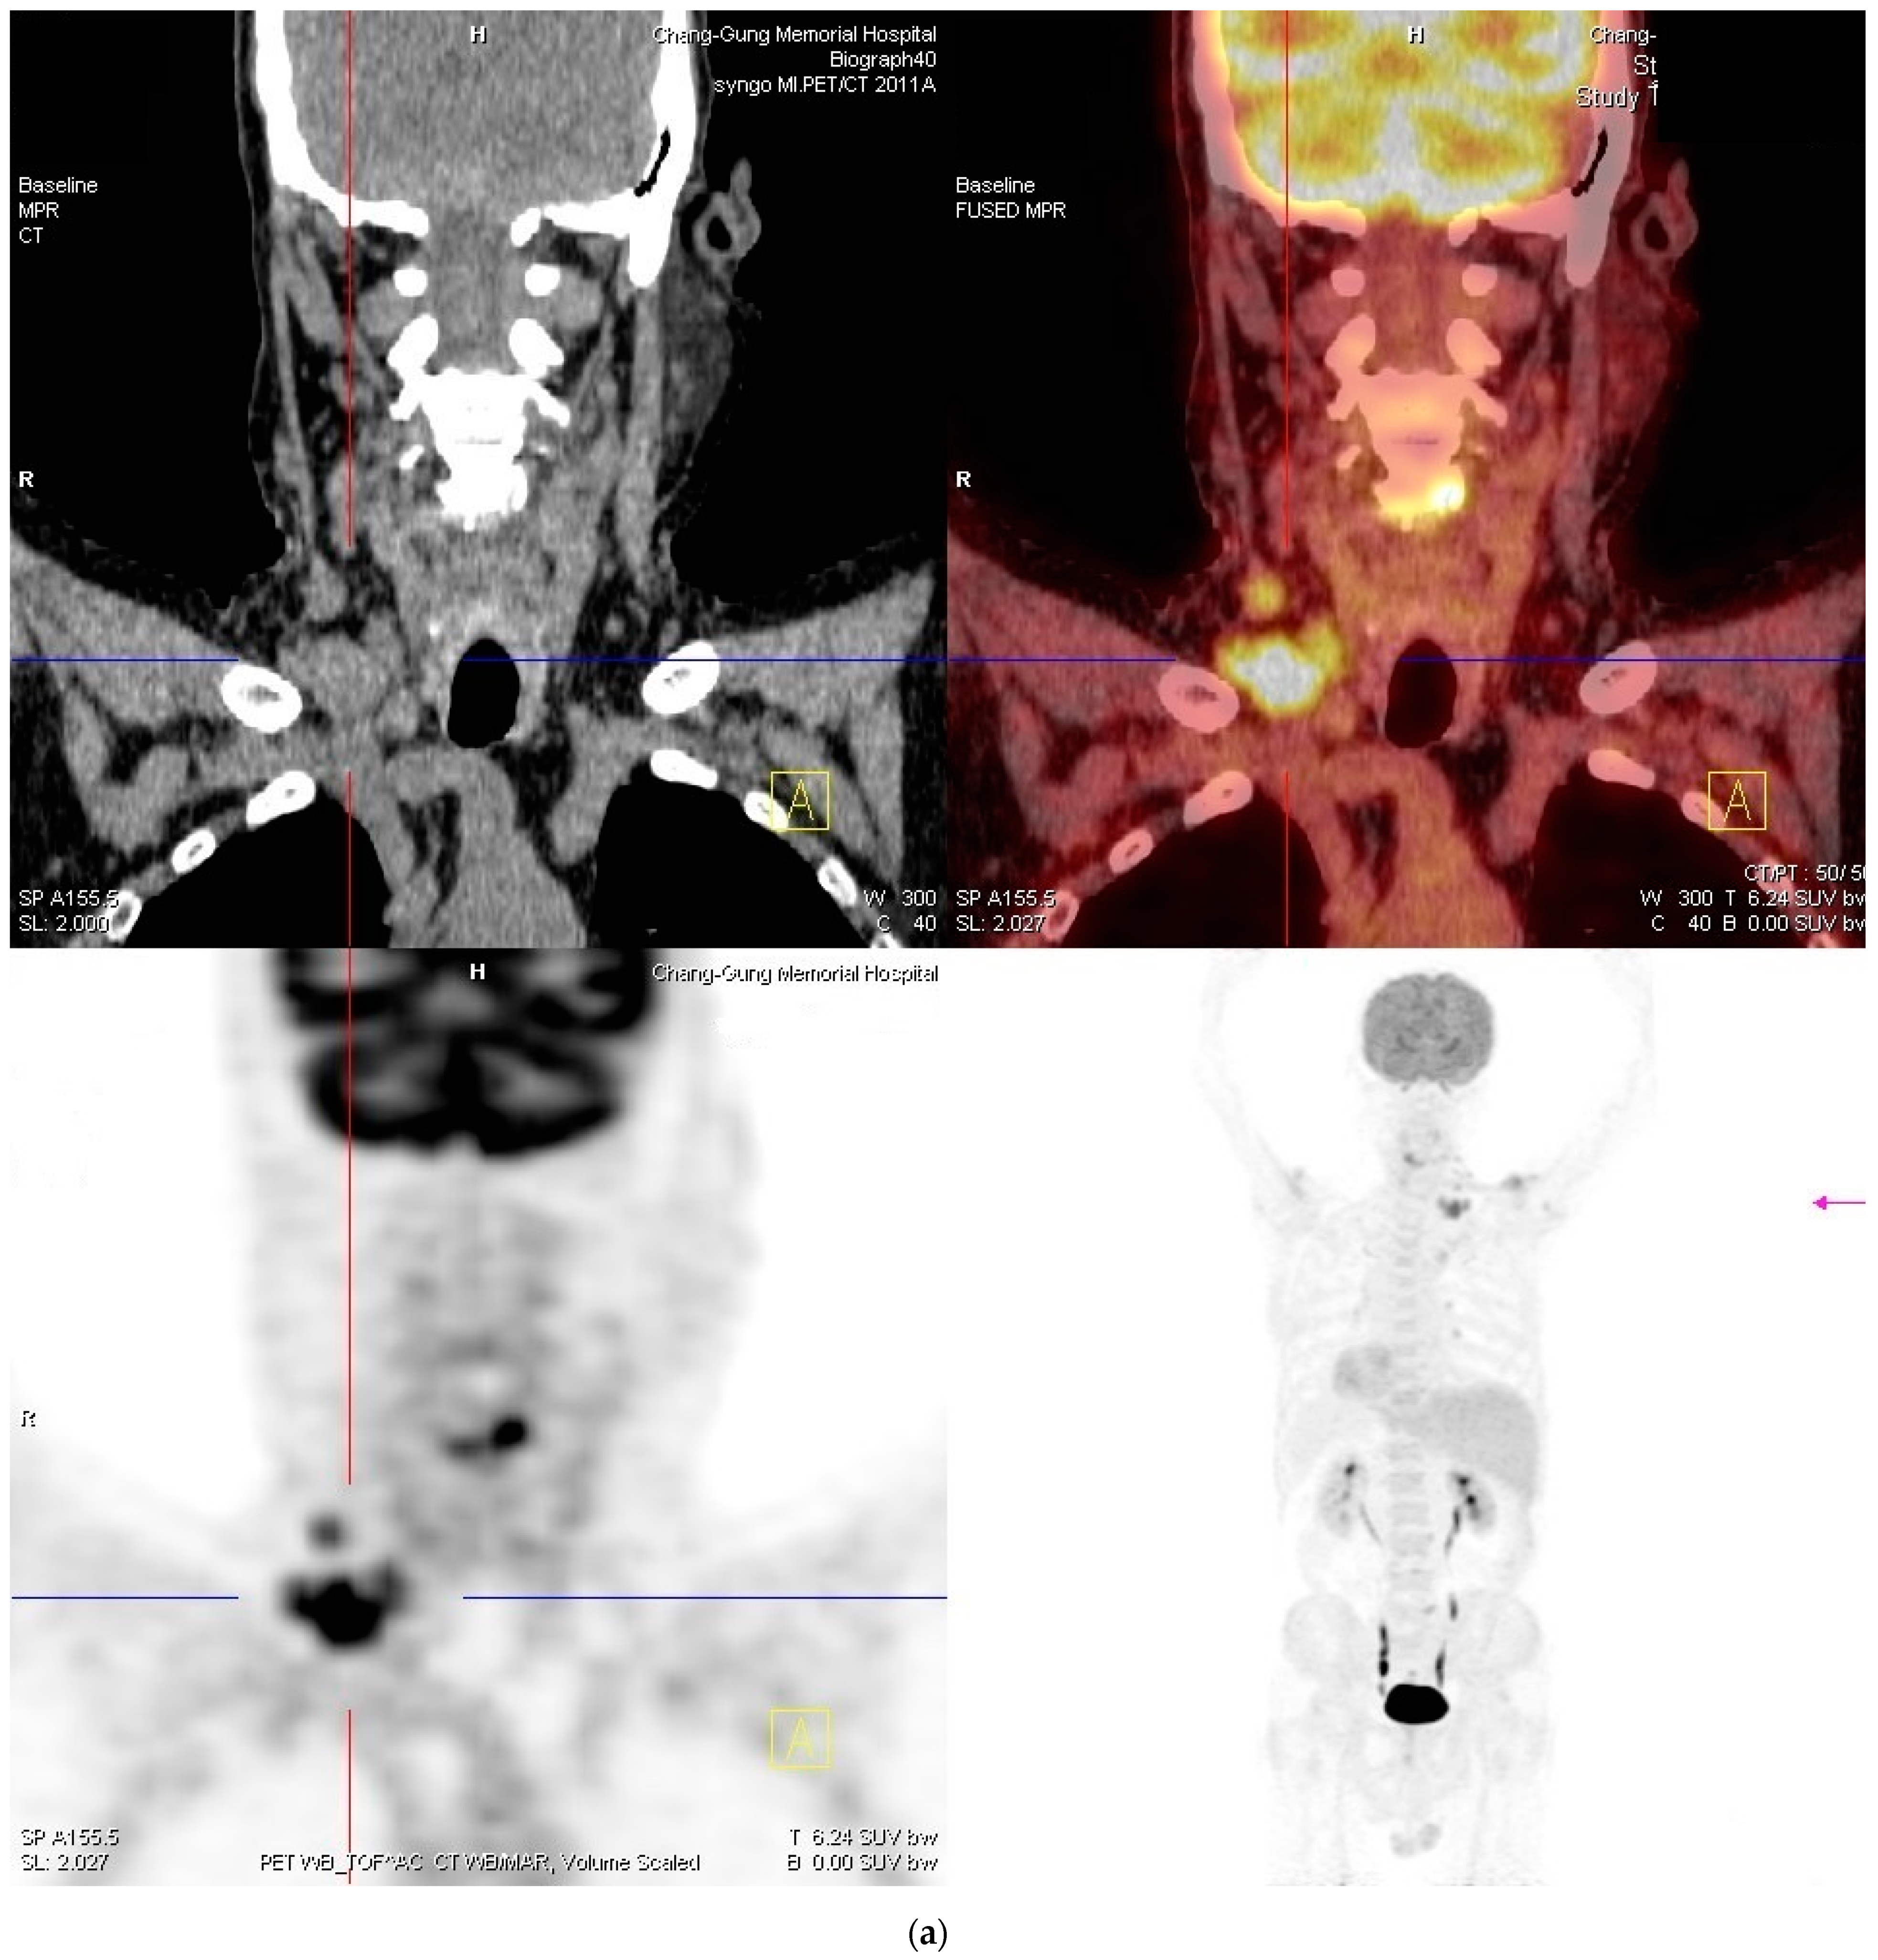

2. Case Report